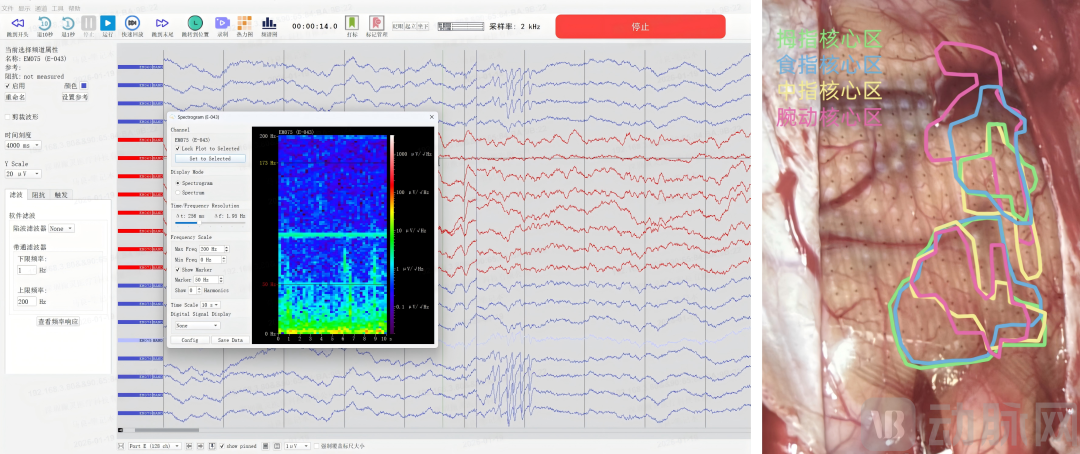

微灵医疗的脑机接口解码系统,能够实时接收术中脑电生理信号,并通过AI算法进行快速在线解码,生成生理与功能图谱。当患者于术中被唤醒,并执行特定指令(如说话或活动肢体)时,系统能够识别并定位对应脑功能区的神经电活动特征,从而助医生清晰地区分出“可切除的病灶区”与“必须保护的功能区”。这项精准的脑功能导航技术,为实现“术前术中监测—智能辅助诊断—实时手术导航”一体化的智能诊疗模式奠定了基础。

微灵医疗高通量神经电生理采集系统采集电生理信号(左)

手部精细运动任务功能图谱展示(右)

图源微灵医疗

该脑机接口解码系统包括微灵医疗柔性薄膜高密度电极阵列,高通量脑电生理信号采集器,AI增强的快速解码器软件等技术产品。正是基于这一完整的产品技术栈,该系统实现了“信号采集”与“数据解析”的高效协同。